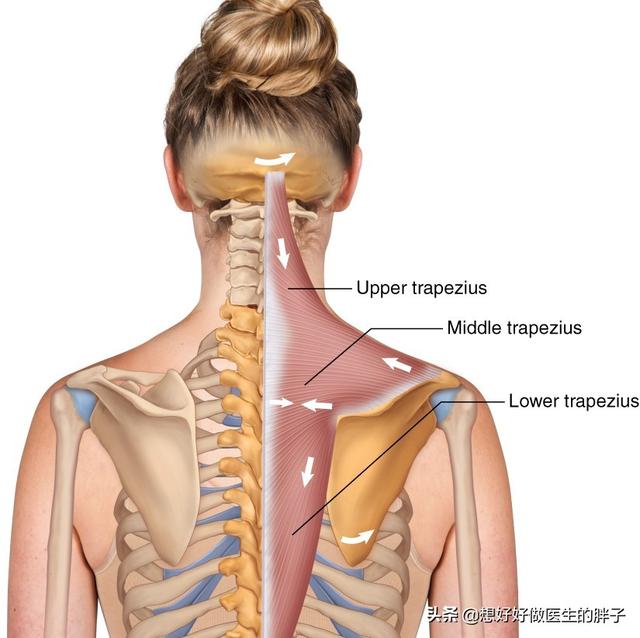

Beaucoup de mes amis pensent queUn cou est un cou, une épaule est une épaule, un dos est un dosque les trois n'ont pas grand-chose à voir l'un avec l'autre, en fait, cette idée est biaisée, de la part des étudiants en médecine, nous devrions prendre l'exemple de l'école de médecine.颈, épaule, dosRegardez-le comme un seul, à partir d'un seul muscle, et donnez une brève analyse de ce muscle, qui est lele muscle trapèze (du haut du dos et du cou)。

Si vous regardez de près, vous verrezCe trapèze.inclureBase du crâne, cou, épaules et dosLes muscles trapèzes des deux côtés sont étroitement liés et forment ensemble une structure rhomboïde, qui est essentielle au maintien de l'équilibre de la colonne vertébrale.Stabilisation du dosIl joue un rôle très important dans l'accomplissement de multiples activités au niveau du cou, des épaules et du dos.Le muscle trapèze est divisé en faisceaux supérieur, moyen et inférieur, et les différentes parties de la contraction permettent d'effectuer des mouvements différents。

Ce n'est qu'un seul muscle, il y en a beaucoup d'autres dans le cou, les épaules et le dos.chairqui sont toutes reliées entre elles, y comprisFascia sous la peauC'est aussi une seule et même chose, on ne peut pas séparer le cou, les épaules et le dos, je crois qu'il faut le comprendre.